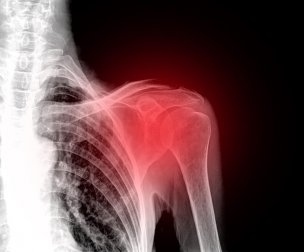

Saiba como diminuir a dor no ombro, uma situação muito incômoda e incapacitante, já que a articulação do ombro nos permite interagir com o ambiente de maneira eficiente.

Existem diferentes tipos de lesões que podem causar dor, inflamação e incapacidade de se mover. Além disso, a inflamação pode se tornar crônica se não for tratada a tempo.

Primeiro de tudo, você deve saber que a dor no ombro é mais comum do que você imagina e, mais importante, que tem solução. Há momentos em que será necessário consultar um médico se a dor envolver luxações e fraturas. Estas duas situações são geralmente devido a lesões nessa área.

As fraturas são o resultado de um osso quebrado. Elas geralmente ocorrem devido a quedas ou lesões de alto impacto, como acidentes esportivos ou com veículos motorizados. Elas causam dor e inflamação severas.